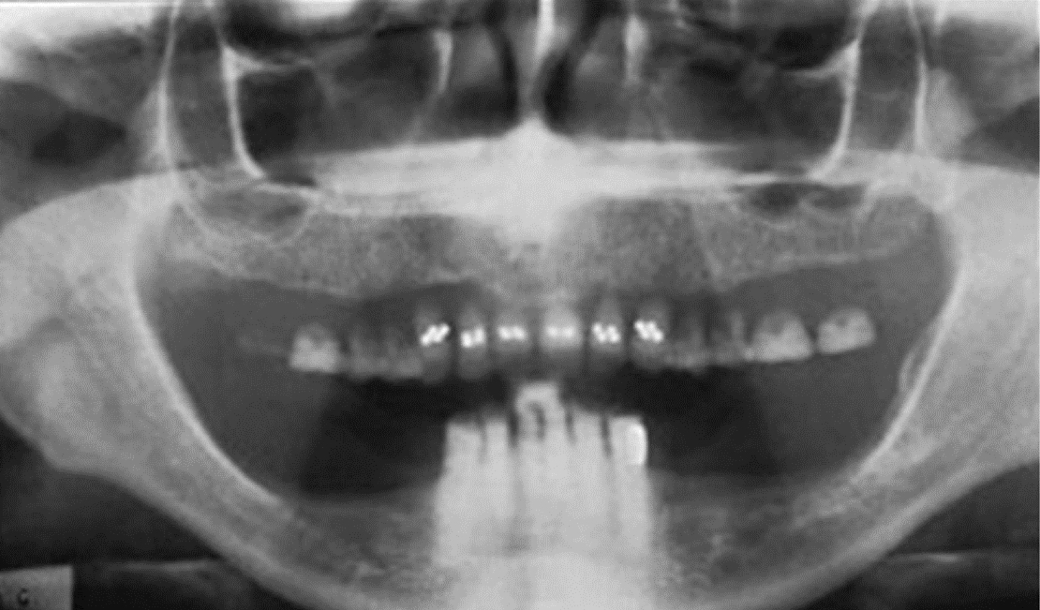

Removable partial denture

Earrings

Nose ring